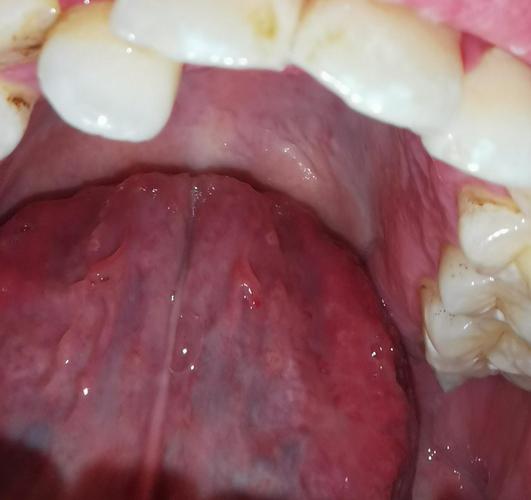

hpv口腔早期症状图片,感染hpv舌头两侧图

请问这个是口腔感染hpv的状态吗

病情描述: 与hpv患者接吻过,无法确定她口腔是否有,看自己口腔怪怪的

口腔的尖锐湿疣和hpv感染